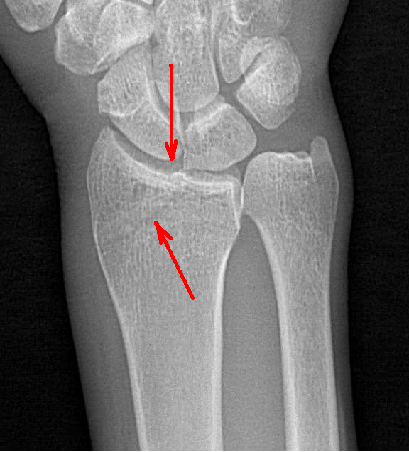

動態(tài)DR具備高清攝像和動態(tài)透視、實(shí)時(shí)高清點(diǎn)片等多種功能,對于隱匿性肋骨骨折的診斷優(yōu)勢明顯。